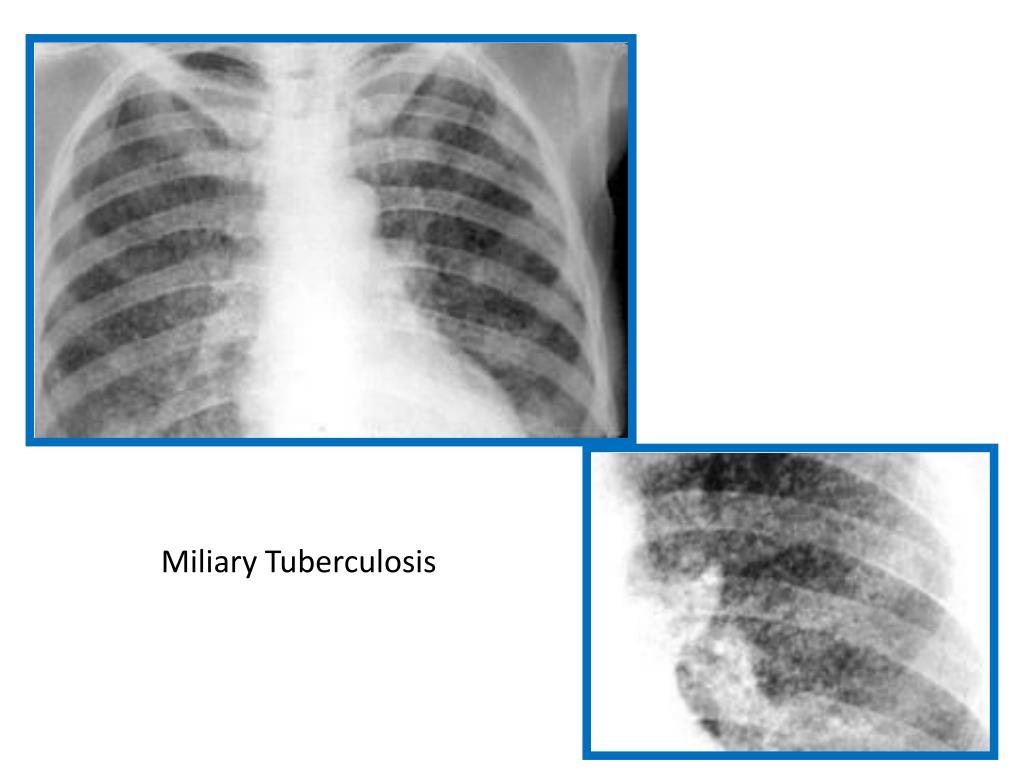

4. Miliary TB = Blood-borne dissemination • May present acutely, but more frequently is characterised by 2-3 weeks of fever, night sweats, anorexia, weight loss and a dry cough. • Hepatosplenomegaly may be present and the presence of a headache may indicate co-existent tuberculous meningitis. • Auscultation of the chest is frequently normal, although with more advanced disease widespread crackles are evident. • Fundoscopy may show choroidal tubercles. • The classical appearances on chest X-ray are those of fine 1-2 mm lesions ('millet seed') distributed throughout the lung fields, although occasionally the appearances are coarser. • Anaemia and leucopenia may be present • Negative tuberculin skin test in 50% of pateints. • Confirmation ; by biopsy (granulomas and/or acid-fast bacilli demonstrated) of liver or bone marrow

5. Miliary Tuberculosis